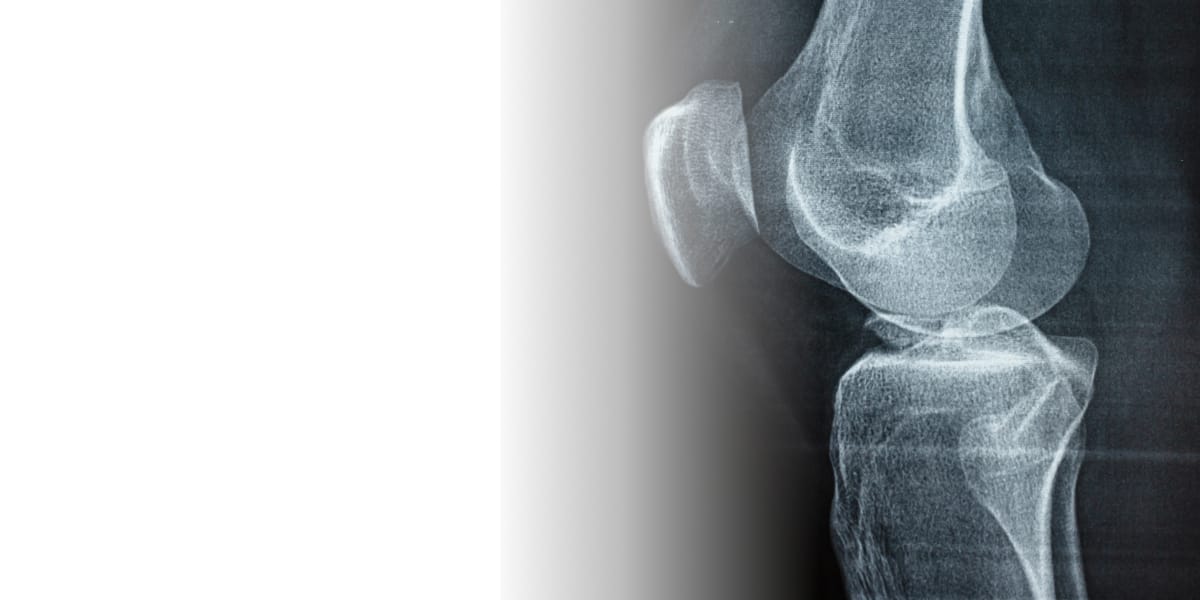

КТ суставов — это метод лучевой диагностики с использованием рентгеновских лучей. Принцип работы компьютерной томографии заключается в следующем: томограф вращается вокруг исследуемой области, пропуская лучи через тело пациента. Детекторы измеряют их, а компьютер обрабатывает данные, создавая послойные (и часто трехмерные) изображения костей и мягких тканей сустава для детальной диагностики.

Компьютерная томография и магнитно-резонансная томография (МРТ) работают по разным принципам: КТ использует рентгеновские лучи, а МРТ — магнитное поле. Благодаря этому они подходят для разных задач. КТ отлично визуализирует костные структуры, поэтому она предпочтительна для диагностики переломов, трещин, вывихов и других костных повреждений. МРТ, напротив, лучше демонстрирует мягкие ткани, такие как связки, сухожилия, хрящи и мышцы.

Что показывает КТ суставов?

Компьютерная томография суставов позволяет детально рассмотреть внутренние структуры и выявить различные проблемы, такие как:

- травмы: переломы, вывихи, трещины костей

- износ суставов: артроз (остеоартроз), остеопороз

- воспаления: артрит, бурсит, синовит

- опухоли: доброкачественные и злокачественные образования в костях и мягких тканях

- инфекции: остеомиелит (воспаление кости)

- врожденные особенности развития суставов

КТ помогает детально оценить состояние костей, образующих сустав, а также околосуставных мягких тканей, что важно для точной диагностики и правильного лечения.